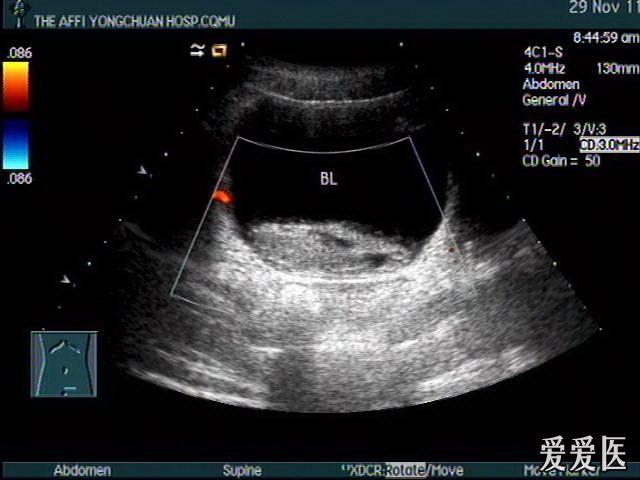

右肾挫伤,膀胱血凝块——zengerya - 超声医学讨论版 - 爱爱医医学

图片尺寸640x480